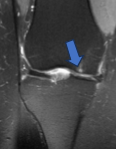

Lesiones de ligamentos de rodilla: Las roturas del ligamento cruzado anterior (LCA) son frecuentes en deportes por giros bruscos, presentando crujido audible e inestabilidad. El ligamento cruzado posterior (LCP) suele dañarse por impactos directos en la tibia, causando dolor en la corva y riesgo de artrosis. El ligamento femoropatelar medial (LFPM) es clave para la estabilidad rotuliana, y su lesión provoca sensación de fallo en la rodilla, especialmente tras luxaciones. Las roturas de ligamentos colaterales (medial/lateral) ocurren por torceduras laterales, generando dolor al forzar la apertura o cierre articular. El tratamiento varía desde rehabilitación para lesiones parciales hasta reconstrucción artroscópica en roturas completas, siendo esencial un diagnóstico preciso mediante resonancia magnética y exploración física especializada.